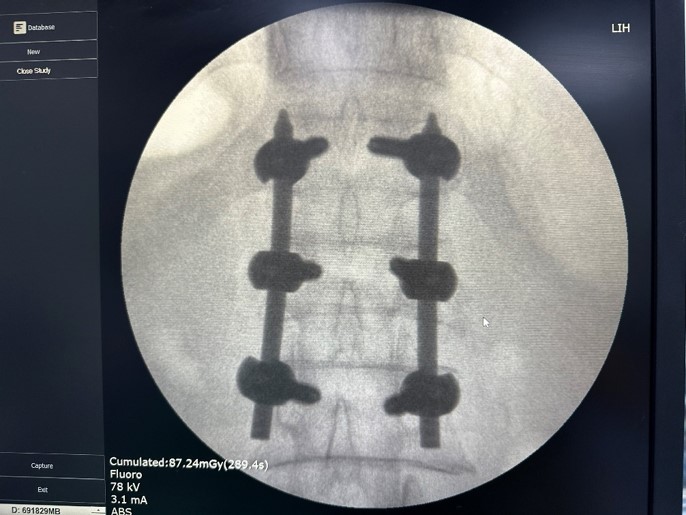

Nhanh chóng, người bệnh được thực hiện phẫu thuật cố định cột sống bản lề ngực thắt lưng bằng phương pháp bắt vít qua da. Ca phẫu thuật thành công, hậu phẫu bệnh nhân ổn định, đau ít hơn so với phẫu thuật mổ mở do vết mổ chỉ là các vết rạch da nhỏ( mổ mở là đường rạch da dài) và không gây tổn thương các cấu trúc dây chằng phía sau cột sống. Ngày thứ 2 sau mổ bệnh nhân đã có thể mặc áo nẹp cột sống hỗ trợ để tập vận động đi lại. Bệnh nhân ra viện sau 5 ngày điều trị.

BSCKI. Nguyễn Mạnh Thuần – Khoa Ngoại chấn thương chỉnh hình – người trực tiếp thực hiện ca phẫu thuật cho biết, cố định cột sống bằng bắt vít qua da là phương pháp điều trị hiệu quả với những tình trạng chấn thương cột sống như ca bệnh trên. Phương pháp này có ưu điểm lớn nhất đó là tối thiểu hóa sự xâm lấn vào cơ thể người bệnh, vì kích thước mở da chỉ bằng với kích thước mà vít đi qua. Nếu như trước đây, người bệnh phải chịu một vết mổ dài gây tổn thương cấu trúc dây chằng phía sau cột sống dẫn đến làm chậm quá trình hồi phục và phục hồi chức năng, thì với phương pháp cố định cột sống bằng bắt vít qua da, thời gian hậu phẫu ngắn, giảm nguy cơ tai biến và đặc biệt hiệu quả của phương pháp cao, đảm bảo cột sống chắc chắn, phục hồi sức khỏe của người bệnh ngay sau chấn thương.